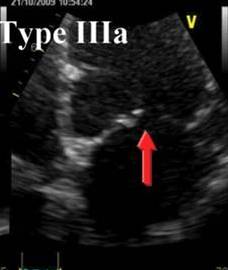

Leaflet thickening. Leaflet motion is restricted during diastole and systole. Shortening of the chordae. Type IIIa Mitral Regurgitation.